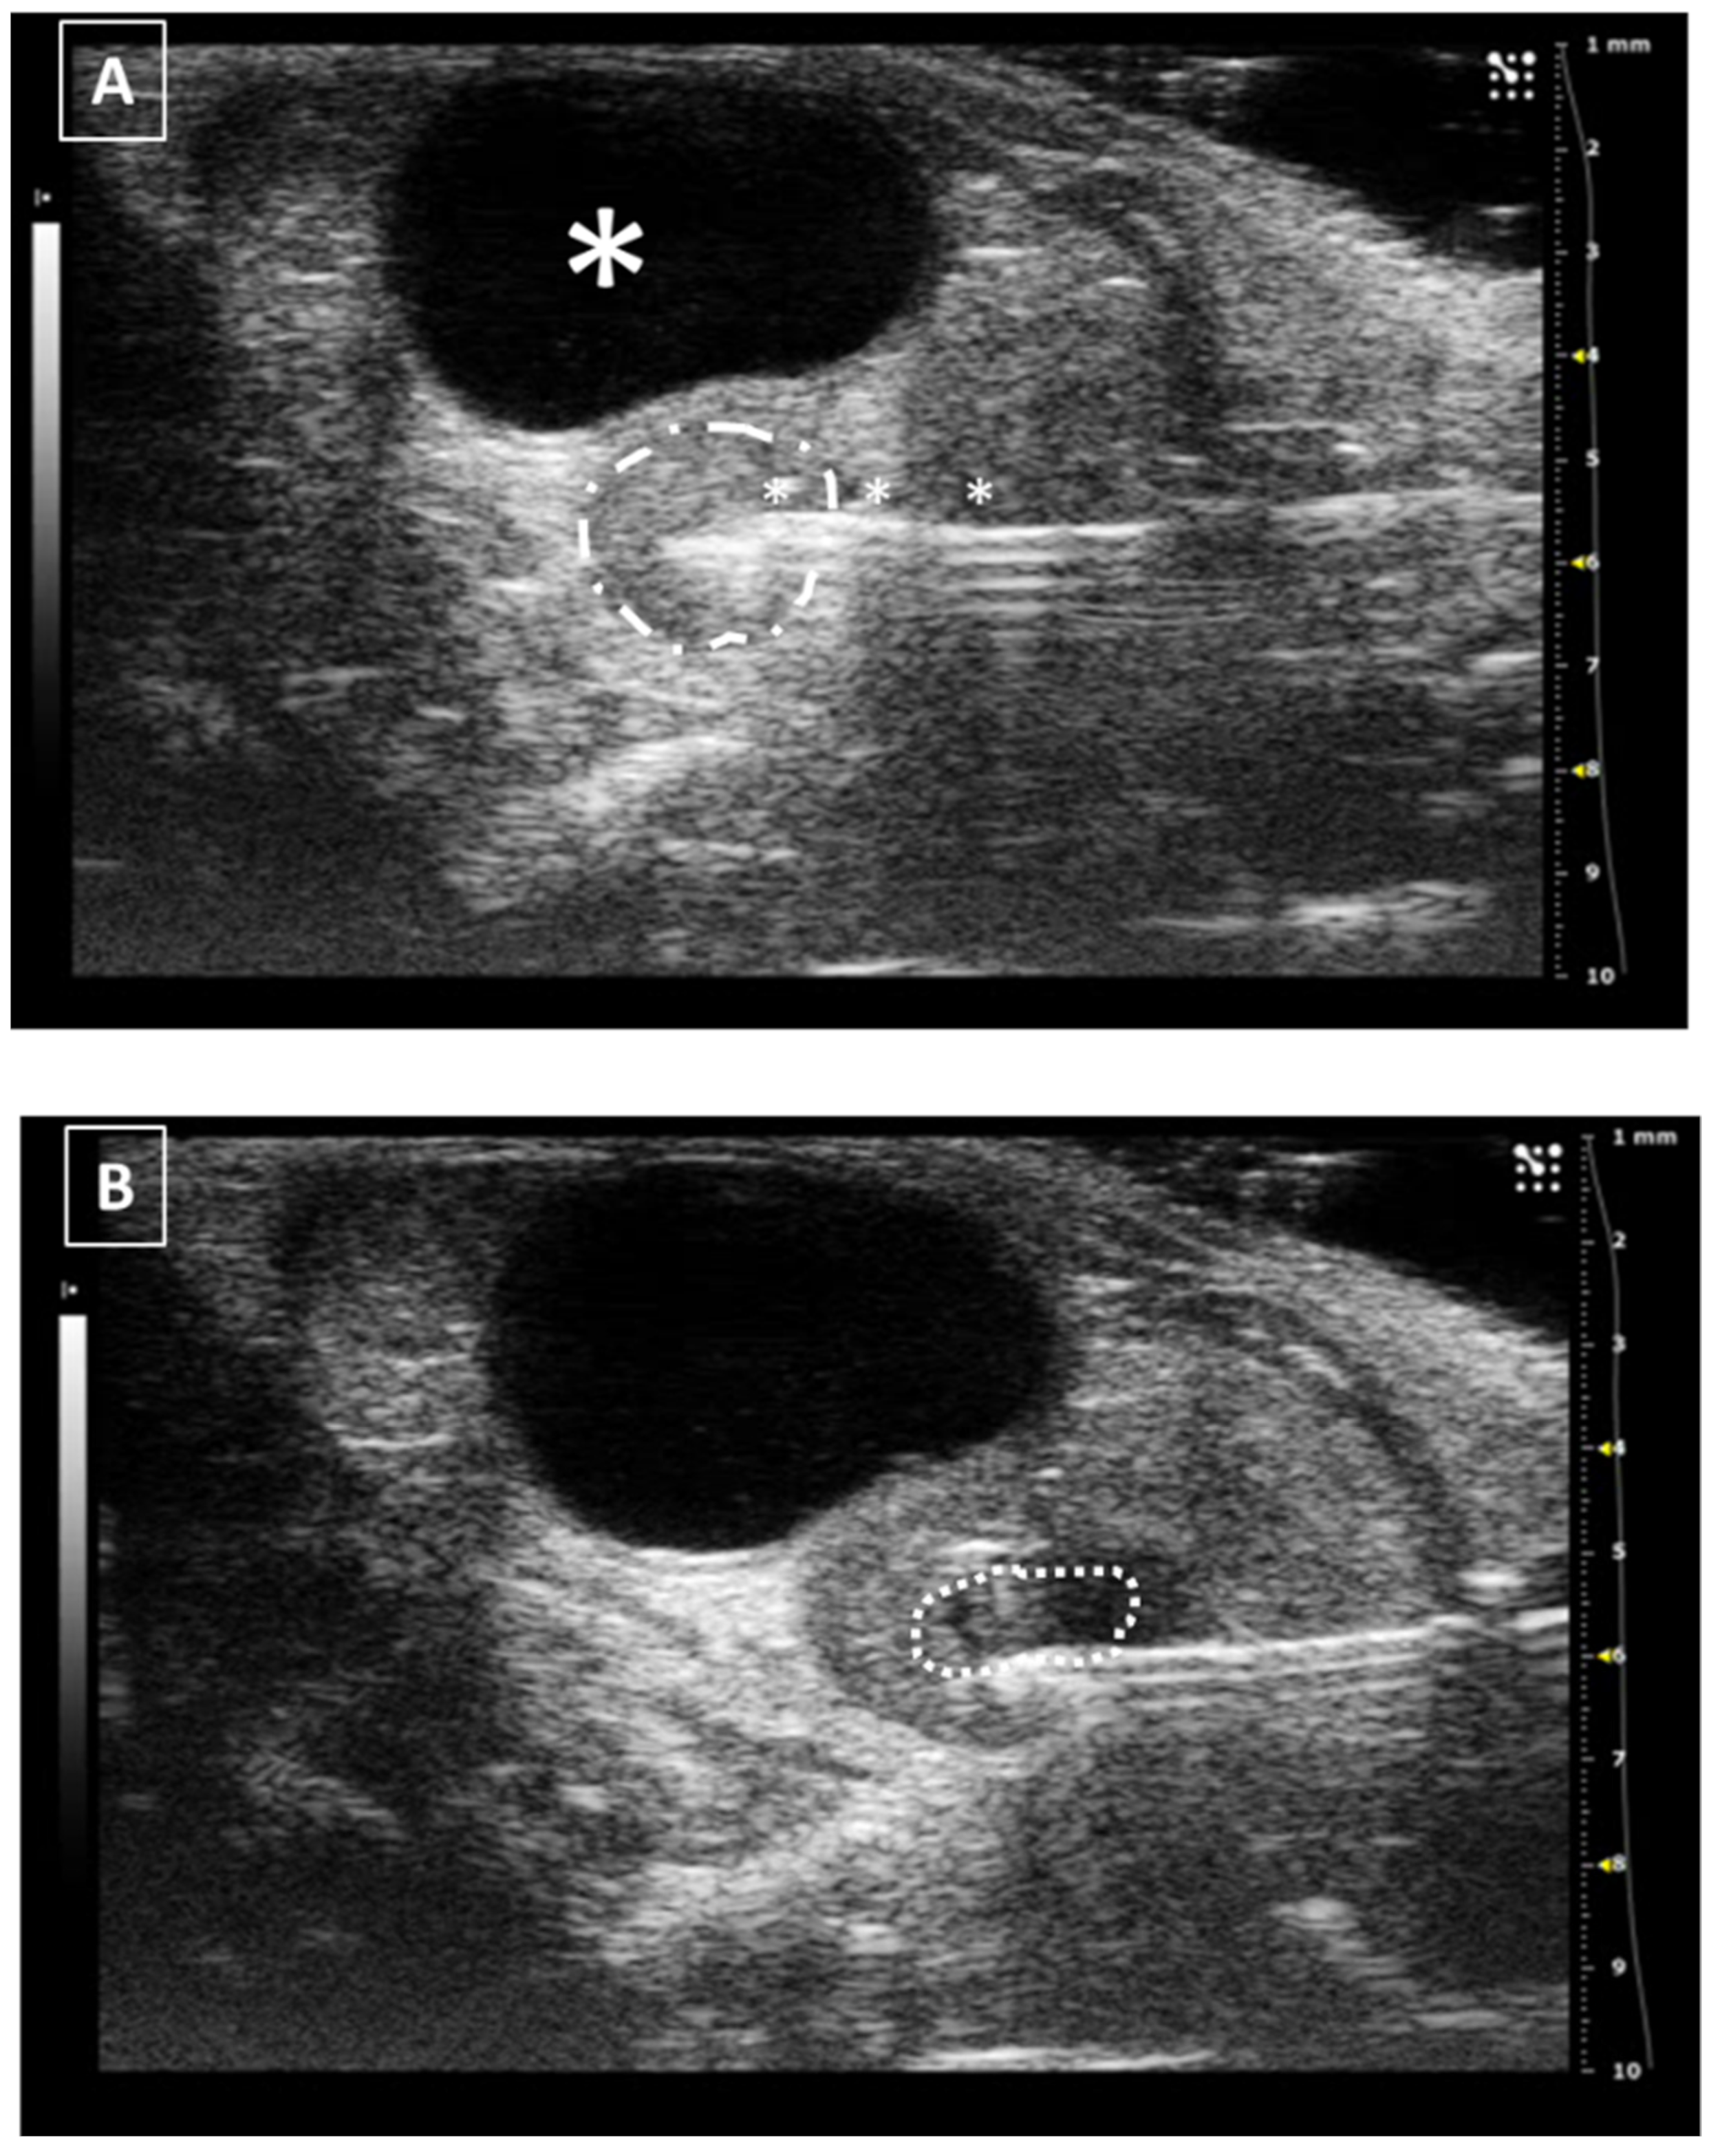

In the same way as the liver and spleen, the kidney biopsy can be performed following the same approach as the injection but pulling the needle plunger instead of pushing it down. Multiple samples can be collected in both the cortical and medullar areas of the organ. An example of a renal injection is shown in Figure 7.

The uterine injection using ultrasonography is one of the most difficult techniques, especially when the organ is in repose (not gravid). The structure is long, thin, and mobile, and the uterine wall is hard. All these characteristics make the intrauterine injection a challenging process. The less mobile part of the uterus is the neck which stays anatomically fixed in place. In this part of the organ, the injection could be feasible. On the other hand, for injecting the uterine horns they should be externally exposed with a surgical opening of the abdomen. For intrauterine injections, the previously published works never went over 30 microliters [37,38,39,40]. Like in the other injections, we should keep the needle in place for some seconds before removing the needle. Figure 8 shows a representative image of a uterine injection.

Figure 7. Intrarenal injection. (A) Injection of the needle into the kidney. Needle is marked with white asterisks and the kidney is surrounded by a dashed line. The injection is performed in the medullar zone of the organ. (B) Administration of the fluid, that is marked with a white asterisk. Images obtained at 40 MHz frequency.

Figure 8. Intrauterine injection. (A) The uterus is punched but no fluid is administered. The needle is marked with white asterisks. The uterus is surrounded by a dashed line. The urinary bladder is marked with a big white asterisk. (B) Same structure after administration. The fluid collection is marked with a dotted line. Images obtained at 40 MHz frequency.